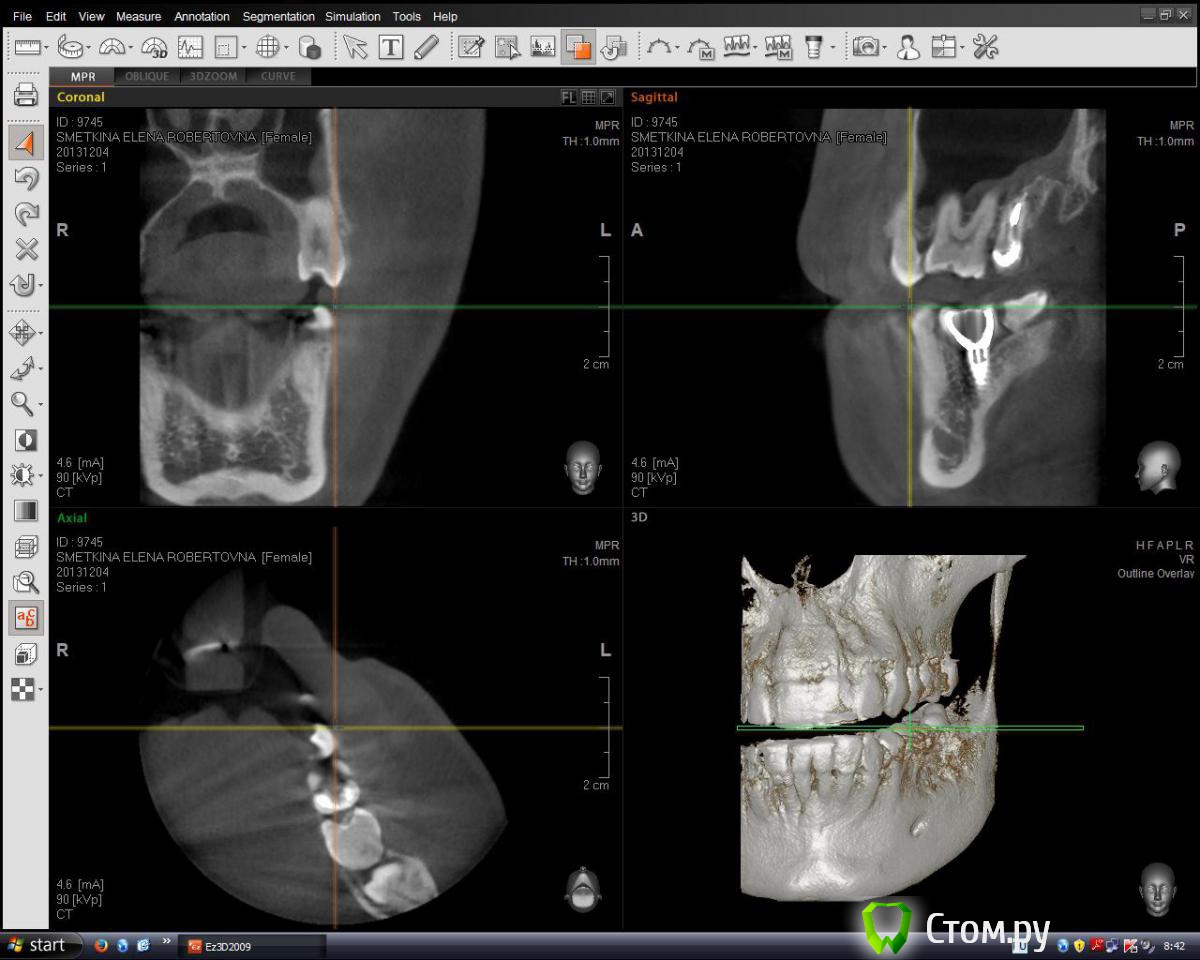

englishlady Опубликовано 18 марта, 2014 Автор Поделиться Опубликовано 18 марта, 2014 Уважаемые врачи, здравствуйте.Я размещаю свою КТв нескольких ракурсах.Можно что-нибудь сказать о судьбе 27 зуба, о прогнозе для импланта 36, и возможности сохранения 37 зуба при удалении нижней восьмерки?Заранее спасибо. Ссылка на комментарий

englishlady Опубликовано 18 марта, 2014 Автор Поделиться Опубликовано 18 марта, 2014 Вроде установила. Надеюсь, что это то, что нужно. В первую очередь интересует зуб 27.http://i021.radikal.ru/1403/a3/9e9ce0c90c64.png[/url] Ссылка на комментарий

Mane Опубликовано 20 марта, 2014 Поделиться Опубликовано 20 марта, 2014 Скорее всего стоит. Но окончательно ясно станет после снятия коронки. Ссылка на комментарий

englishlady Опубликовано 21 марта, 2014 Автор Поделиться Опубликовано 21 марта, 2014 Спасибо большое за ответ. А можно что-нибудь сказать по предоставленным снимкам про имплант 36. У него номальный прогноз? И нужно ли в ближайшее время удалять 38 зуб? Просто все врачи, у которых я была, сказали, что не надо трогать пока сильно не заболит. Объясняли это тем, что тогда нужно будет удалять и 37 зуб. Это дейсвительно так? Ссылка на комментарий

Bier Опубликовано 21 марта, 2014 Поделиться Опубликовано 21 марта, 2014 у имплантата нормальный прогноз.про 38 - надо смотреть эту зону на КТ Ссылка на комментарий